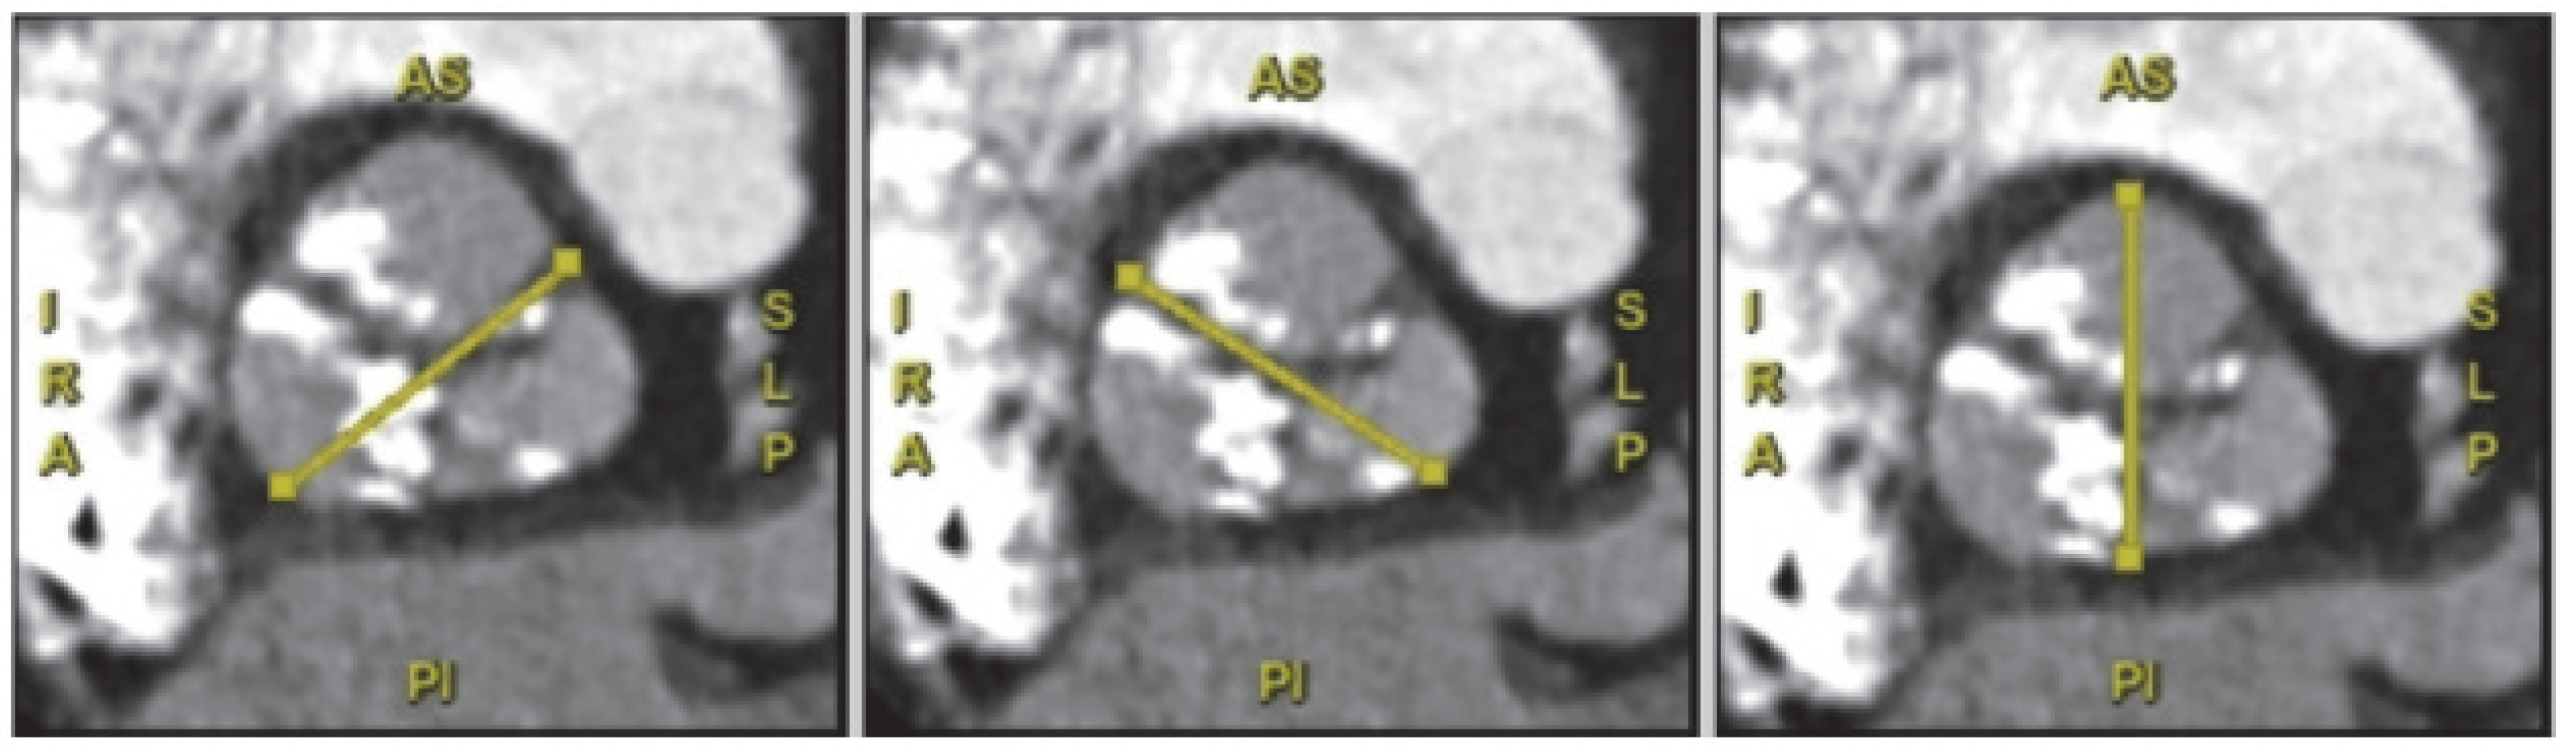

In mitral valve replacement, left ventricular outflow tract (LVOT) obstruction is a potential complication of transcatheter mitral valve replacement (TMVR). During TMVR, a patient’s native outflow tract can be altered, with the resulting LVOT sometimes referred to as the “neo-LVOT”. Preprocedural CT imaging, which can simulate the neo-LVOT, is useful for predicting the risk of obstruction. Recently, a study of patients undergoing TMVR found that a neo-LVOT area smaller than 1.7 cm2 at the end-systole posed a high risk of obstruction [52]. Other anatomical characteristics analyzed with MSCT are the presence and conformation of calcium at the level of the annulus (MAC), mitral anterior leaflet length to recognize high-risk of LVOT obstruction, and annulus diameter to choose prosthesis size.